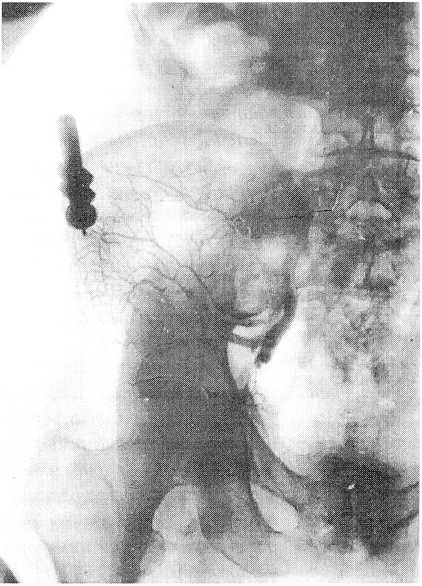

Рис. 2. Рентгенограмма после введения 70 мл контраста

При препарировании, кроме вышеназванных сосудов, красящая масса была обнаружена в общей подвздошной вене, на всем протяжении подчревной вены, венозных сплетениях пресакральной области, в венах заднего листка париетальной брюшины подвздошной области и области таза на стороне введения, в забрюшинной клетчатке и забрюшинных лимфатических узлах. В области таза, помимо париетальных сосудов, красящая масса обнаруживалась в венах тазовой клетчатки, в сосудах околоматочного венозного сплетения, а также в тонких венозных стволах тканей в области маточных труб и яичников. Отмечено распространение красящей массы на значительном протяжении в центральном направлении по венам забрюшинного пространства и венам наружного венозного сплетения позвоночного столба. Красящая масса определялась также в нижней полой и воротной венах, венах солнечного сплетения, а также в области поясничного сплетения на стороне введения, поясничного и крестцового отделов пограничного симпатического ствола, в почке и правой доле печени. Следует отметить, что степень заполнения красящей массой вен различных тканей таза была неодинаковой. Во всех случаях многочисленные вены, окрашенные массой Герата-Акиловой в синий цвет, были обнаружены в подвздошной мышце и ее фасции. В подвздошной мышце она проникала в различные по калибру сосуды (рис. 3).